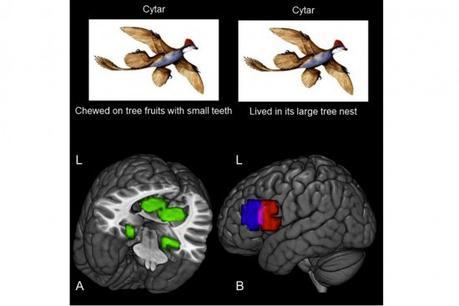

Un grupo de investigadores en la Universidad Carnegie Mellon decidió averiguarlo con un estudio en el que participaron 16 personas. Todas ellas recibieron información sobre ocho animales extintos, incluyendo sus dietas y su hábitat. Andrew Bauer, líder del estudio, y el profesor de neurociencia cognitiva Marcel Just, utilizaron un sistema de resonancia magnética funcional para obtener imágenes precisas mientras todos estos nuevos conceptos eran invocados por el cerebro. Cada uno de esos conceptos generaron una especie de "firma", y con la ayuda de una plataforma de software, los investigadores fueron capaces de reconocer en qué animal estaba pensando cada participante en un momento determinado, lo que podría interpretarse como "leer la mente".

Otro aspecto muy interesante es que cuando dos o más animales comparten un aspecto, las "firmas"del cerebro poseen cierta similitud, y una vez que los detalles sobre un animal fueron asimilados por completo, permanecen intactos aún frente a la llegada de nueva información, lo que expone la llamada "durabilidad neural" de aquello que aprendemos. La idea es que el estudio permita desarrollar nuevos métodos de aprendizaje en el futuro, pero lo más importante, entender mejor la pérdida de conocimiento causada por condiciones como daño cerebral, demencia, y la siempre presente enfermedad de Alzheimer.